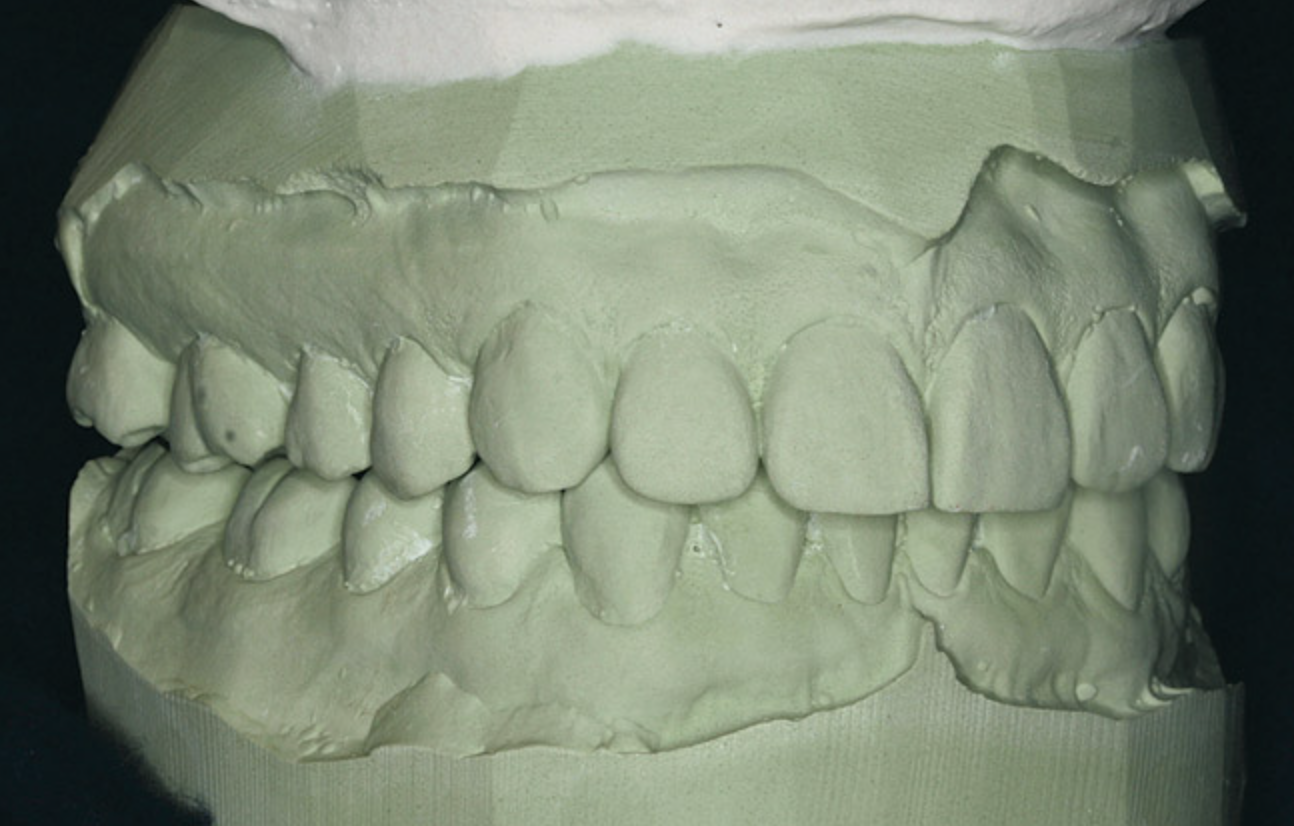

The dental midline can be improved within limits by restorative procedures. However, if orthodontic alignment is to be performed, the orthodontist plans treatment to ensure the position and vertical axis of the midline is harmonious with the facial esthetics (Figure 1).

The proportions of the teeth make a significant difference in the balance of the smile. Most restorative dentists are keenly aware of the importance of the golden proportion (Figure 2). When the maxillary lateral incisors are pegged or undersized, the orthodontist should be asked to redistribute the spaces. By positioning teeth properly, the restorative dentist can fabricate restorations to ideal proportions. When anterior teeth are crowded or broken down with loss of space, orthodontic alignment allows the natural proportions to be restored.

Figure 1  Dental midlines should be as close to coincident as possible. Gingival height of maxillary lateral incisors should be even with a line between the gingival height of the central incisor and canine to 1.5 mm below that line.

Figure 1

Figure 2   A balanced appearance of the anterior teeth is represented by a

Figure 2